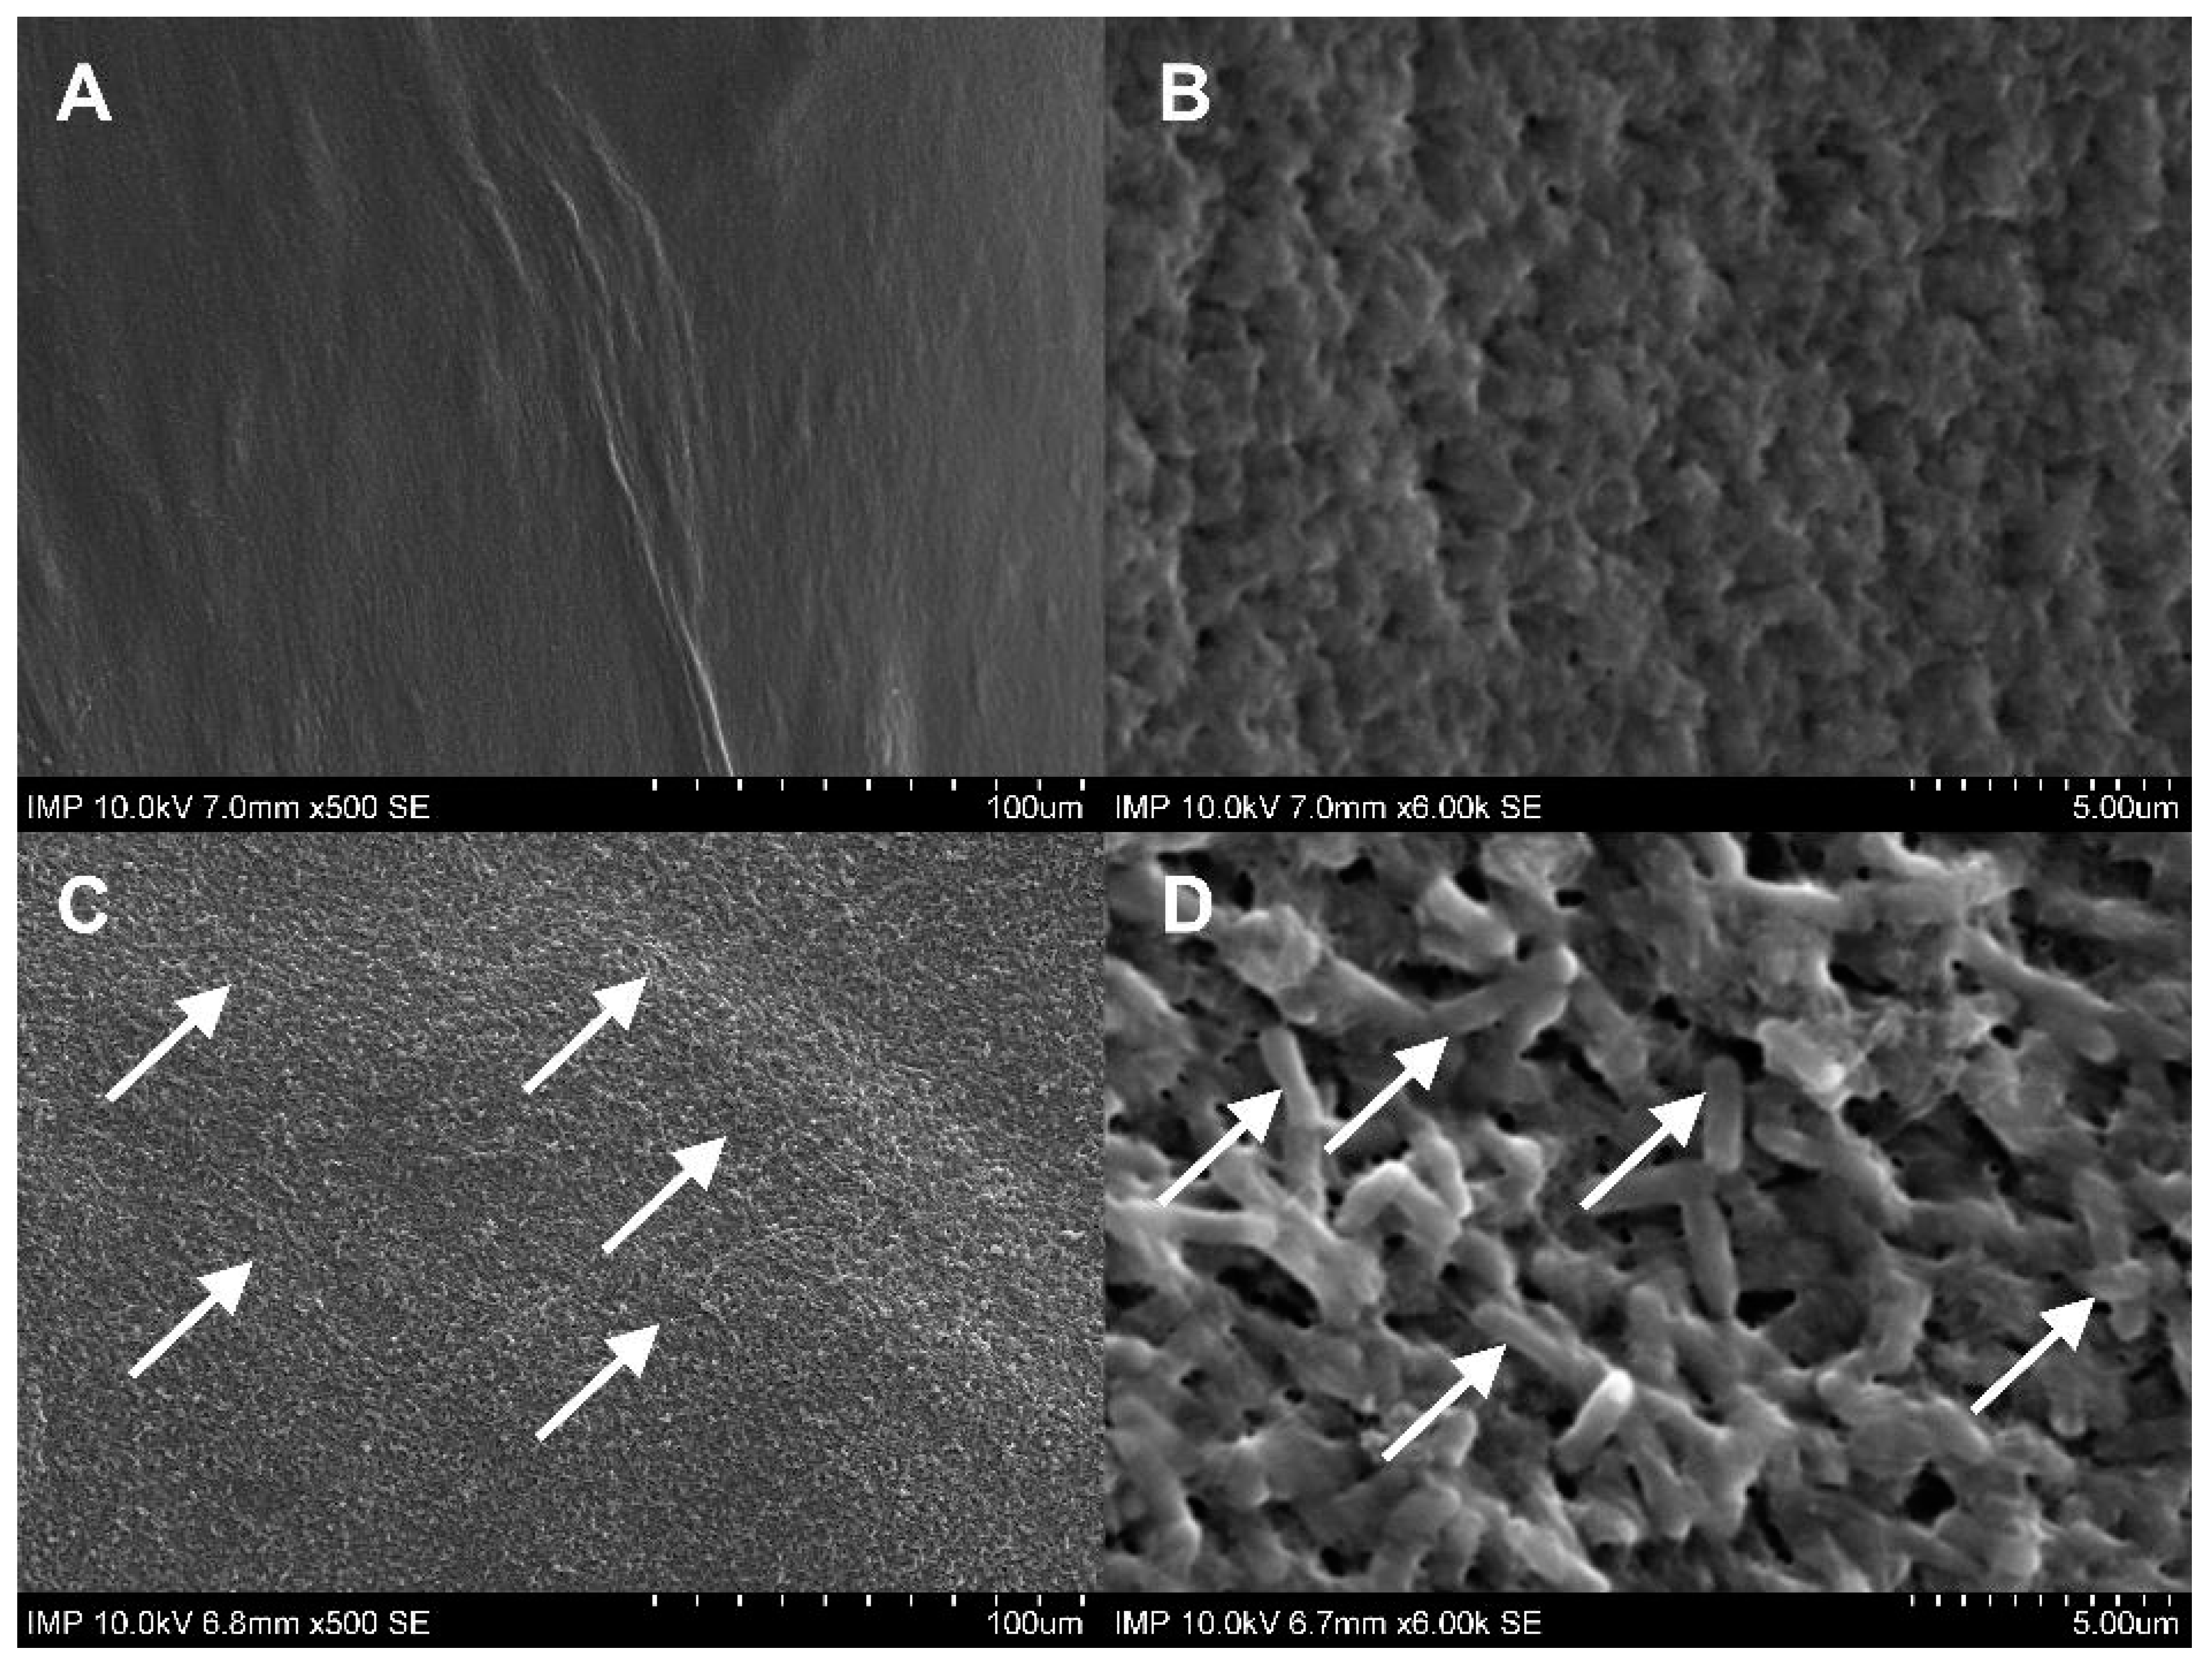

2.1. Surface Coating of the Grafts

4.2.5. Scanning Electron Microscopy